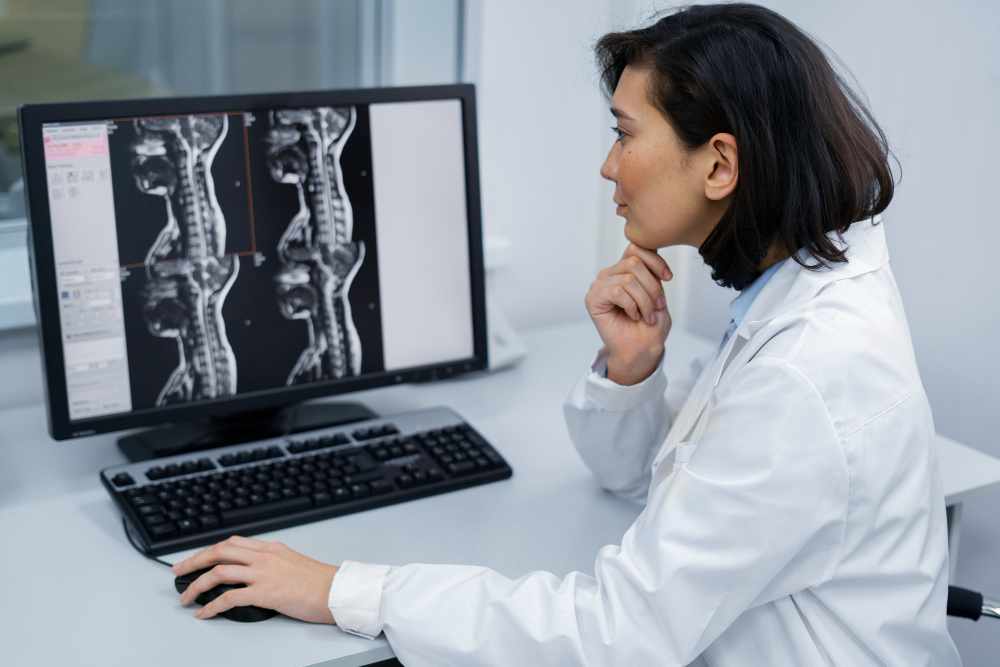

How MRI of the Lumbar Spine Helps Diagnose Back Pain and Other Spinal Issues

What is an MRI Lumbar Spine? An MRI Lumbar Spine is a special scan that uses strong magnets and radio waves. It creates clear pictures